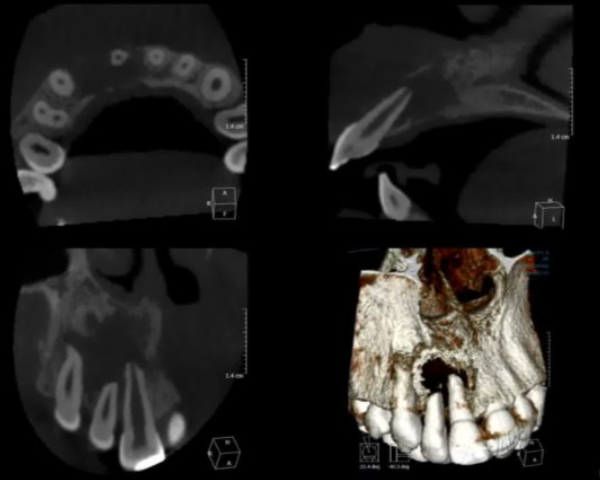

when may a cone beam CT be used when assessing periapical inflamm pathology?

often used for troubleshooting when plain films can’t answer ur clinical question